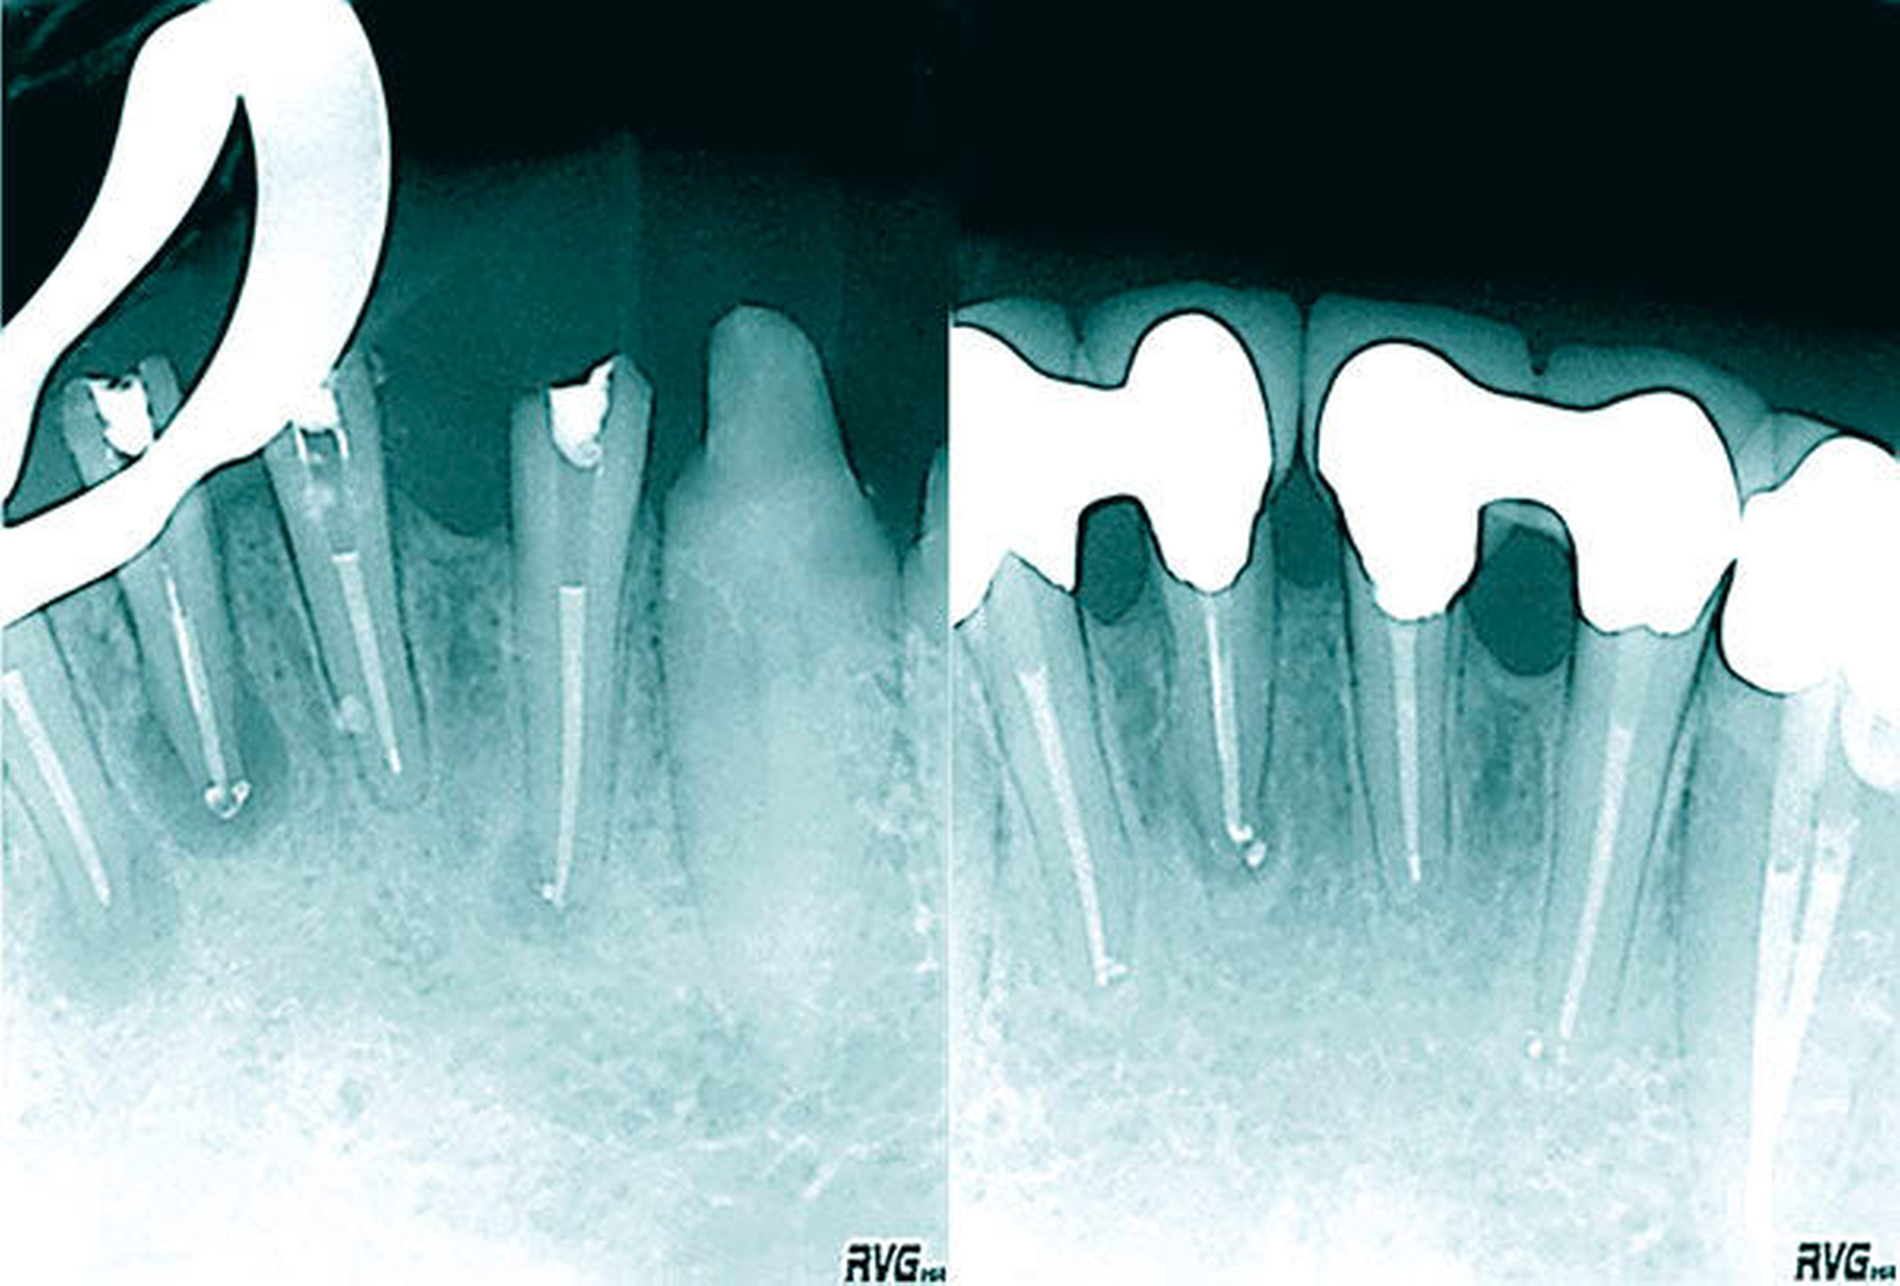

Aktuell werden häufig Rekonstruktionsverfahren mit einem Mikro-CT angefertigt, um die Anatomie der Zähne in situ zerstörungsfrei untersuchen zu können (Abbildung 4). Klinische Untersuchungen werden heute mit DVT-Aufnahmen unterstützt. Die Auflösung – oder auch Voxelgröße – mit bis zu 80 µm darf jedoch nicht darüber hinweg täuschen, dass durch natürliche Bewegungen des Patienten (wie Atmung und Puls) eine sichere Darstellung der Anzahl und Verzweigungen der Wurzelkanäle unmöglich ist [Patel, 2009]. Studien auf der Grundlage von DVT-Daten sind deshalb nur Annäherungen an die anatomische Realität. Die Bestimmung der Anzahl und der Aufteilung des Wurzelkanalsystems unterer Frontzähne mit zweidimensionalen Röntgenaufnahmen weist die größten Abweichungen auf. So variieren die Ergebnisse in klinisch-radiologischen Untersuchungen zum Vorkommen von Wurzelkanalaufteilungen zwischen 1 und 61 Prozent [Arnold, 2010]. Auch exzentrische Projektionen erlauben lediglich eine Abschätzung und ermöglichen keine Gewissheit zur Bestimmung [Oliveira, 2009].

Nach einer eigenen Untersuchung von 400 unteren Schneidezähnen lässt sich die Aufteilung der Wurzelkanäle erst 3 mm unterhalb der Schmelz-Zement-Grenze ermitteln (Abbildungen 10 und 11).

Die geringe Größe der klinischen Zahnkrone mit maximal 4 bis 5 mm Breite oder eine gedrehte oder gekippte Zahnstellung allein sind große klinische Herausforderungen, das Wurzelkanalsystem im Fall einer endodontischen Behandlung vollständig darstellen zu können. Die tiefen Aufteilungen als Folge einer Dentinbrücke lassen sich ohne Nutzung eines Dentalmikroskops nur mit erheblichem Zahnhartsubstanzverlust darstellen, so dass der Langzeiterhalt des Zahnes mit der erhöhten Gefahr einer Vertikalfraktur kompromittiert wird. Bei alters- oder reizbedingten Obliterationen des Wurzelkanalsystems erhöht sich darüber hinaus das Risiko einer lateralen Wurzelperforation oder Instrumentenfraktur [Kvinnsland, 1989] (Abbildungen 16a und 16b).

Die mikrobielle Infektion und die unvollständige Wurzelkanalbehandlung lassen sich durch allein chirurgisch resektive Verfahren nicht korrigieren (Abbildungen 17 bis 20). Sofern eine retrograde Präparation, Desinfektion und ein bakteriendichter Verschluss gelingen, kann die Infektion eingeschlossen werden. Die orthograde Revision im Verlauf der antimikrobiellen Therapie ermöglicht unter mikroskopischer Sicht eine vollständige Reinigung und Desinfektion (Abbildungen 15 bis 17).